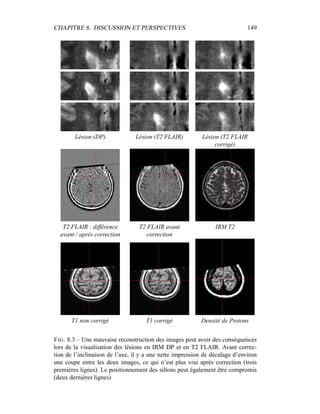

– Image Orientation (Patient) (

−→

Ox,

Oy) donne, dans le repère IRM, les 2 vec-

teurs du repère de la coupe 2D.

– Pixel Spacing (Vx, Vy) donne, dans le repère IRM, la taille des deux vecteurs

du repère de la coupe 2D.

– Slice Thickness Vz donne l’épaisseur de la coupe, ce qui permet de voir si

les coupes sont jointives ou non.